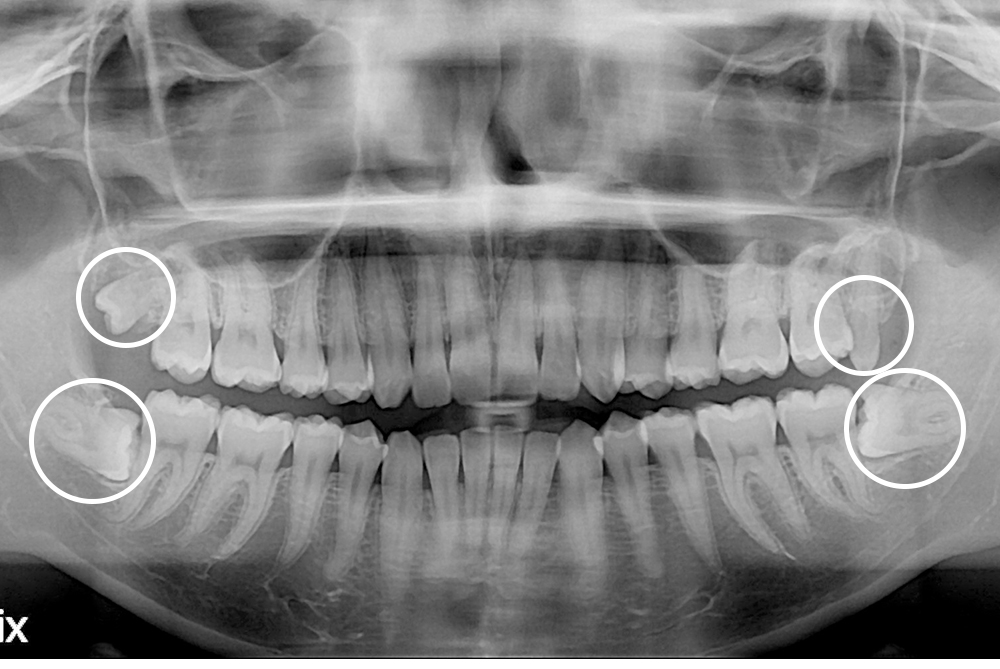

[사랑니] 매복 사랑니 발치

치료전 : 2017-11-21